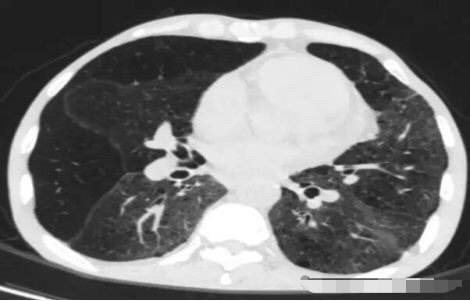

5. 元芳,你看下图是个肺外伤后的表现,也是弥漫性的GGO